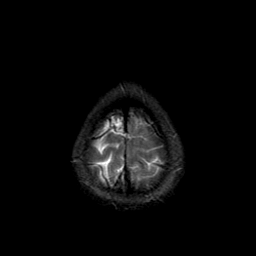

Metastatic bronchogenic carcinoma: T2-weighted MR -- Slice #21

[Home][Help][Clinical] Slice 21